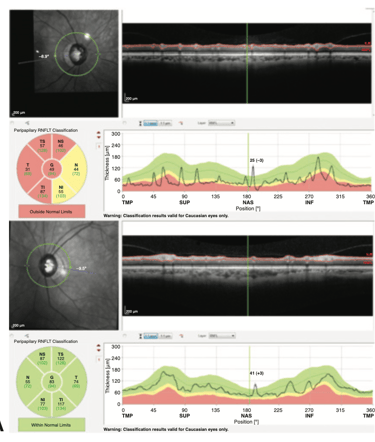

Tomografia de Coerência Óptica (OCT): Para examinar o nervo óptico em detalhes.

Tomografia de Coerência Óptica (OCT)